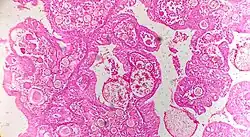

![]() | Serous cystadenoma | Histopathology of serous cystadenoma, with admixed scattered ciliated cells. This case closely resembles normal surface endometrial epithelium of the uterus | Category: Histopathology of ovarian serous cystadenoma | Ovarian cystadenoma |